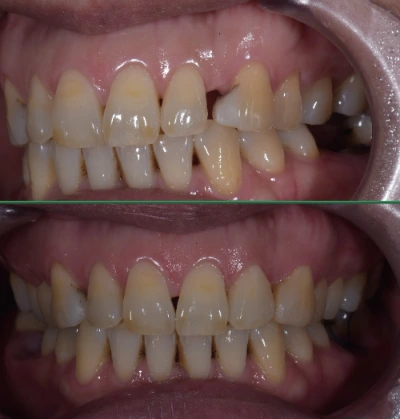

왼쪽 앞니의 레진치료 왼쪽 송곳니 부위의 부적절한 레진을 제거하고 좀 더 자연스럽게 수복..

오른쪽 송곳니의 레진치료 마찬가지로 부적절한 친구들 떼버리고 예쁘게 수복.

오늘도 꽤 괜찮은 레진을 해버리며 안타를 하나 쳤다는 기쁨이 밀려옵니다.